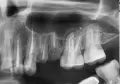

У меня обломаны под корень 4 зуба: четверка и пятерка сверху с обеих сторон. Лет 7-12 назад все они были пролечены, в них были запломбированы каналы, затем они в разное время по частям обломились (сильно разрушены были, пломбы были почти на весь зуб).

С такими, практически отсутствующими (вровень с десной и глубже), я живу уже несколько лет. Не мешают, не болят. Из десны почти не торчат. Цветом черно-коричневые, но это если перпендикулярно заглянуть внутрь лунки — так не видно. Стоматолог сказал, что использовать корни под что-то не удастся — сильно разрушены. Протезировать в ближайшие 3-5 лет я их не планирую: при разговоре их за щеками не видно, есть не мешают, денег на это пока нет (ставить дешевый съемный протез не хочу, обтачивать соседние здоровые зубы тоже).